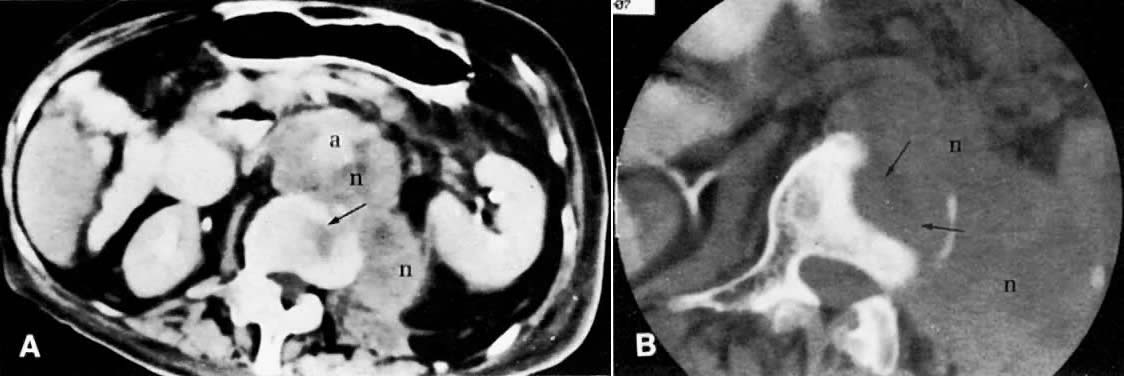

Fig. 45. Metastatic granulosa cell tumor. A. CT scan of the upper abdomen shows a low-density, well-marginated mass ( m) in the right lobe of the liver. B. Lower abdominal CT scan shows a necrotic paracaval mass ( n) consistent with lymphadenopathy. C. CT scan of the pelvis shows an enlarged right external iliac lymph node ( arrow) measuring 1.5 cm in diameter with some necrotic changes seen in its center. ( a, aorta; v, inferior vena cava.)